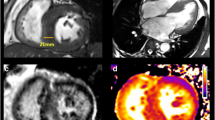

Beside well-established echocardiographic risk factors, there are novel echo parameters derived from 2D STE analysis that may provide additional insight in SCD risk stratification. In a study on more than 3000 HCM patients, abnormal GLS was associated with VA [48]. Mechanical dispersion (i.e., the standard deviation of the time from the onset of systole to maximum contraction for each of the myocardial segments, an expression of heterogeneous contraction and electrical activation) relates to the extent of fibrosis (assessed by CMR) and is an independent predictor of VA (Fig. 3) [49].

Global longitudinal strain (GLS) and myocardial dispersion (MD) in two patients with HCM. MD is calculated as standard deviation of the time from the beginning of ventricular systole to peak longitudinal shortening for each of the myocardial segments. The arrows mark the points of peak longitudinal shortening. A larger distance between arrows (orange line) means an increased MD. a Patient with HCM without history of VAs. b Patient with HCM and history of VAs (NSVTs) has a significantly higher MD. Moreover, patient B had significantly more fibrosis as assessed by CMR compared with patient A. Note that increased MD in patient B is independent of global longitudinal strain (which is better than for patient A), reflecting different functional information. VA ventricular arrhythmias, HCM hypertrophic cardiomyopathy, NSVT nonsustained ventricular arrhythmia, CMR cardiac magnetic resonance